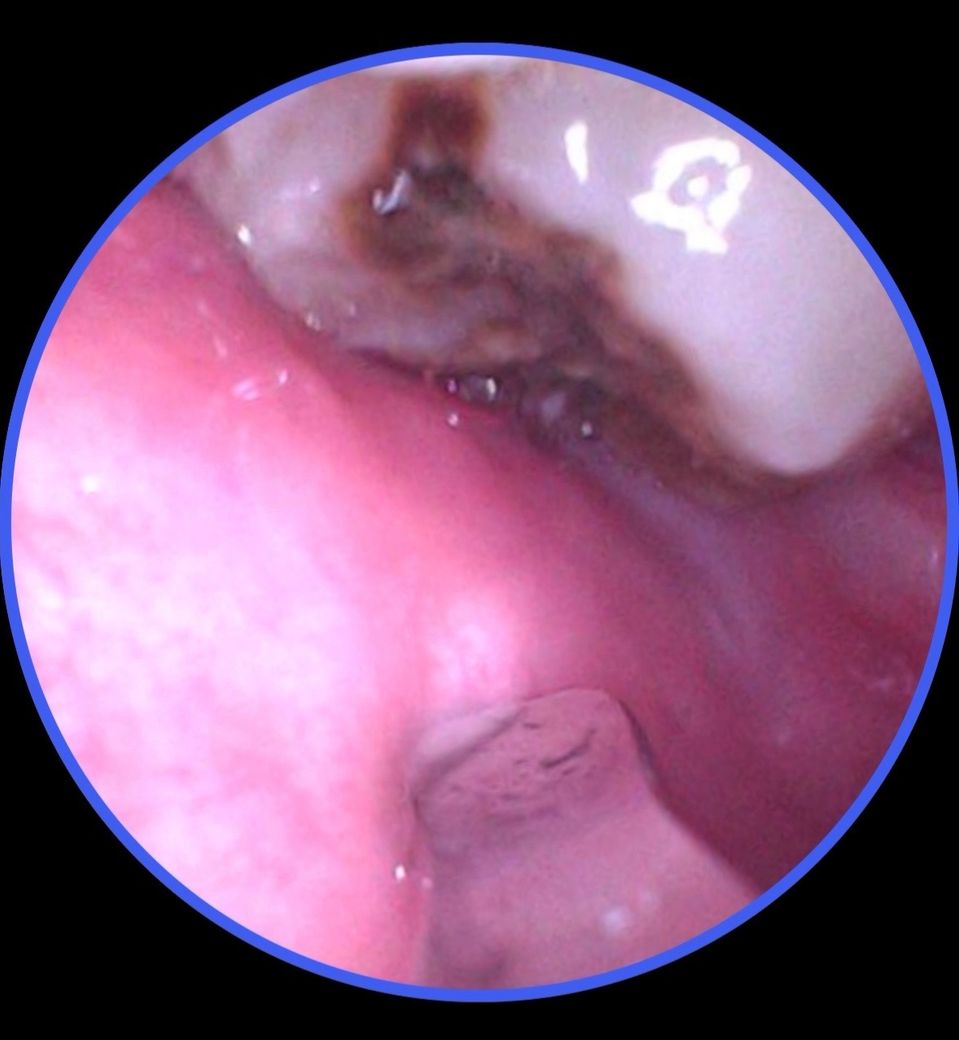

윗니 좌우 사랑니가 칫솔이 잘 닿지 않아서 제대로 양치가 안되고 있다는 느낌은 있었는데, 최근에 내시경 카메라 같은 걸로 볼수 있는 기회가 있어서 봤더니 좌우 사랑니가 다 심하게 갈색이 되어있더라구요. 통증은 없는데 지금 급하게 발치를 헤야하는 상황인지 판단을 위해 질문드립니다.

+추가로 한쪽에는 치아에 붉은 점 같은게 있는데 음식물은 아닙니다. 이건 뭔지도 문의 드립니다.

• 1번 째 사진

최근 내시경으로 확인 후 심하게 갈색으로 변색되어 걱정되시겠어요 엑스레이를 찍지 않아 정확하지 않으나 육안상 판단시 충치의 깊이가 아직 신경을 침범하지 않은 충치라서 통증이 없으신거 입니다 지금처럼 칫솔이 닿는 부위까지 잇솔질을 하시면 충치가 급속하게 진행 되지 않을 것이니 시간 되실때 치과 방문 후 발치 하시면 될 거 같습니다 너무 큰 걱정은 안 하셔도 됩니다

통중이 없으면 발치가 급한 건 아닙니다만 어차피 사랑니는 충치치료가 어렵고 빼야합니다

저정도로 관리가 잘 안되면 사랑니 충치로 인해 구취도 나고, 염증도 생기니 가급적 얼른 빼시는거 추천드립니다